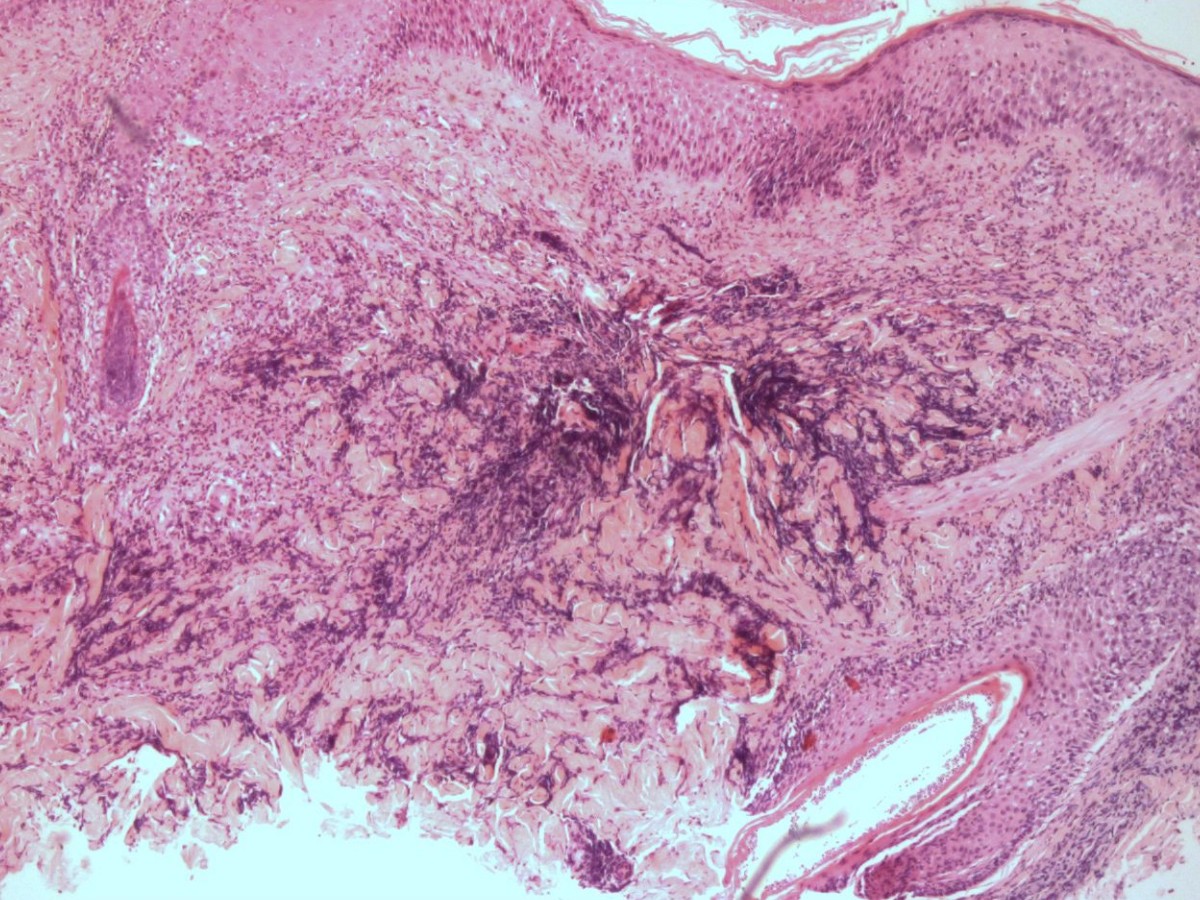

Ook een biopt kan de diagnose aantonen, hierbij zijn schimmeldraden en/of gistbolletjes

te zien in de haarfollikel (PAS kleuring). Bij oppervlakkige mycosen met randschilfering

![Histologie van dermatomycosis barbae, tinea barbae (click on photo to enlarge) [source: www.huidziekten.nl] Histologie van dermatomycosis barbae, tinea barbae](../../../images/dermatomycosis-barbae-PA-1z.jpg) |

![Histologie van dermatomycosis barbae, tinea barbae (click on photo to enlarge) [source: www.huidziekten.nl] Histologie van dermatomycosis barbae, tinea barbae](../../../images/dermatomycosis-barbae-PA-2z.jpg) |

![Histologie van dermatomycosis barbae, tinea barbae (click on photo to enlarge) [source: www.huidziekten.nl] Histologie van dermatomycosis barbae, tinea barbae](../../../images/dermatomycosis-barbae-PA-3z.jpg) |

| mycose

baardstreek (PA) |

mycose